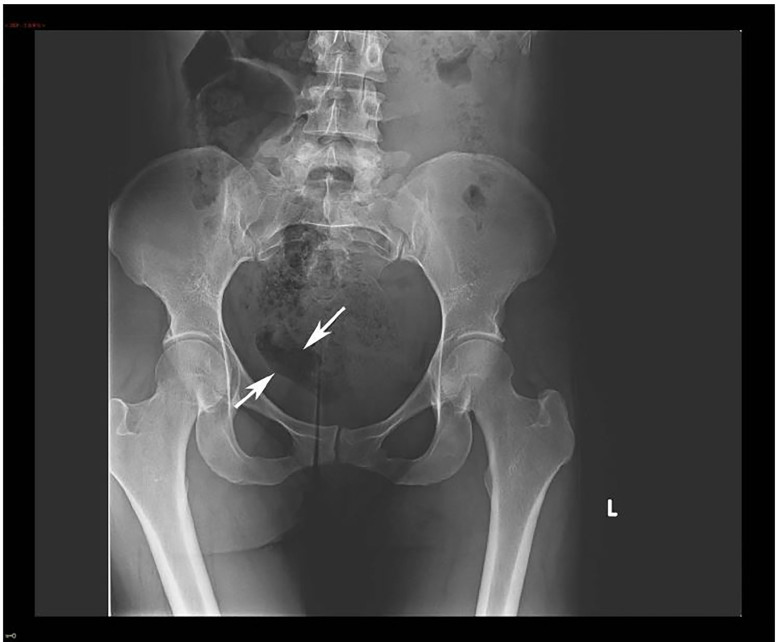

Figure 1. Рентгеновский снимок почек, мочеточников и мочевого пузыря со стрелками, указывающими на область, в которой возможно наличие инородного тела.